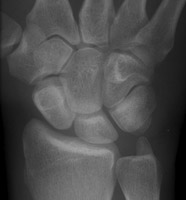

Multiple images of navicular disorientation with dislocation of the scapholunate joint. The scaphoid bone, seen along it long axis, has a ringed cortex appearance. This cortical ring sign is a sign of scapholunate dislocation, This sign was first described in 1970 in young patient with bilateral dislocation of the carpal naviculars. This sign (also known as the signet-ring sign) is caused by the abnormal orientation of the scaphoid.

- Click on the image for a larger versionA - Click on the image for a larger versionB